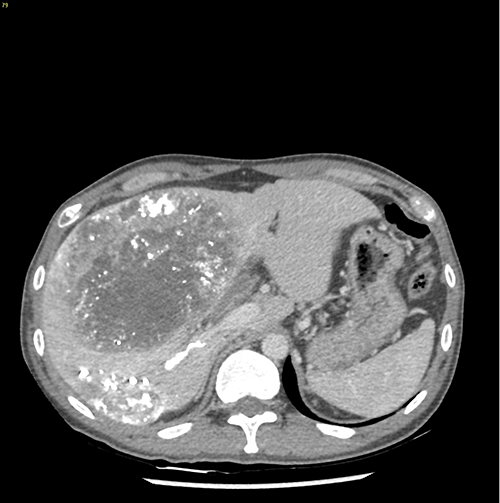

右肝癌---右三肝切除